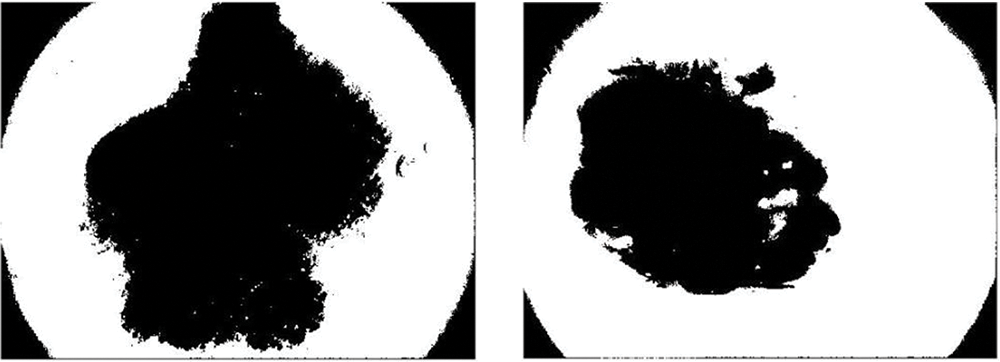

In this paper, Niblack, Sauvola, and binarized Sauvola techniques are used for classifying skin cancer lesions. Fig. 6 illustrates skin cancer images after applying Niblack and Sauvola thresholding in the proposed methodology.

Figure 6: Illustration of skin cancer images after applying Niblack and Sauvola thresholding